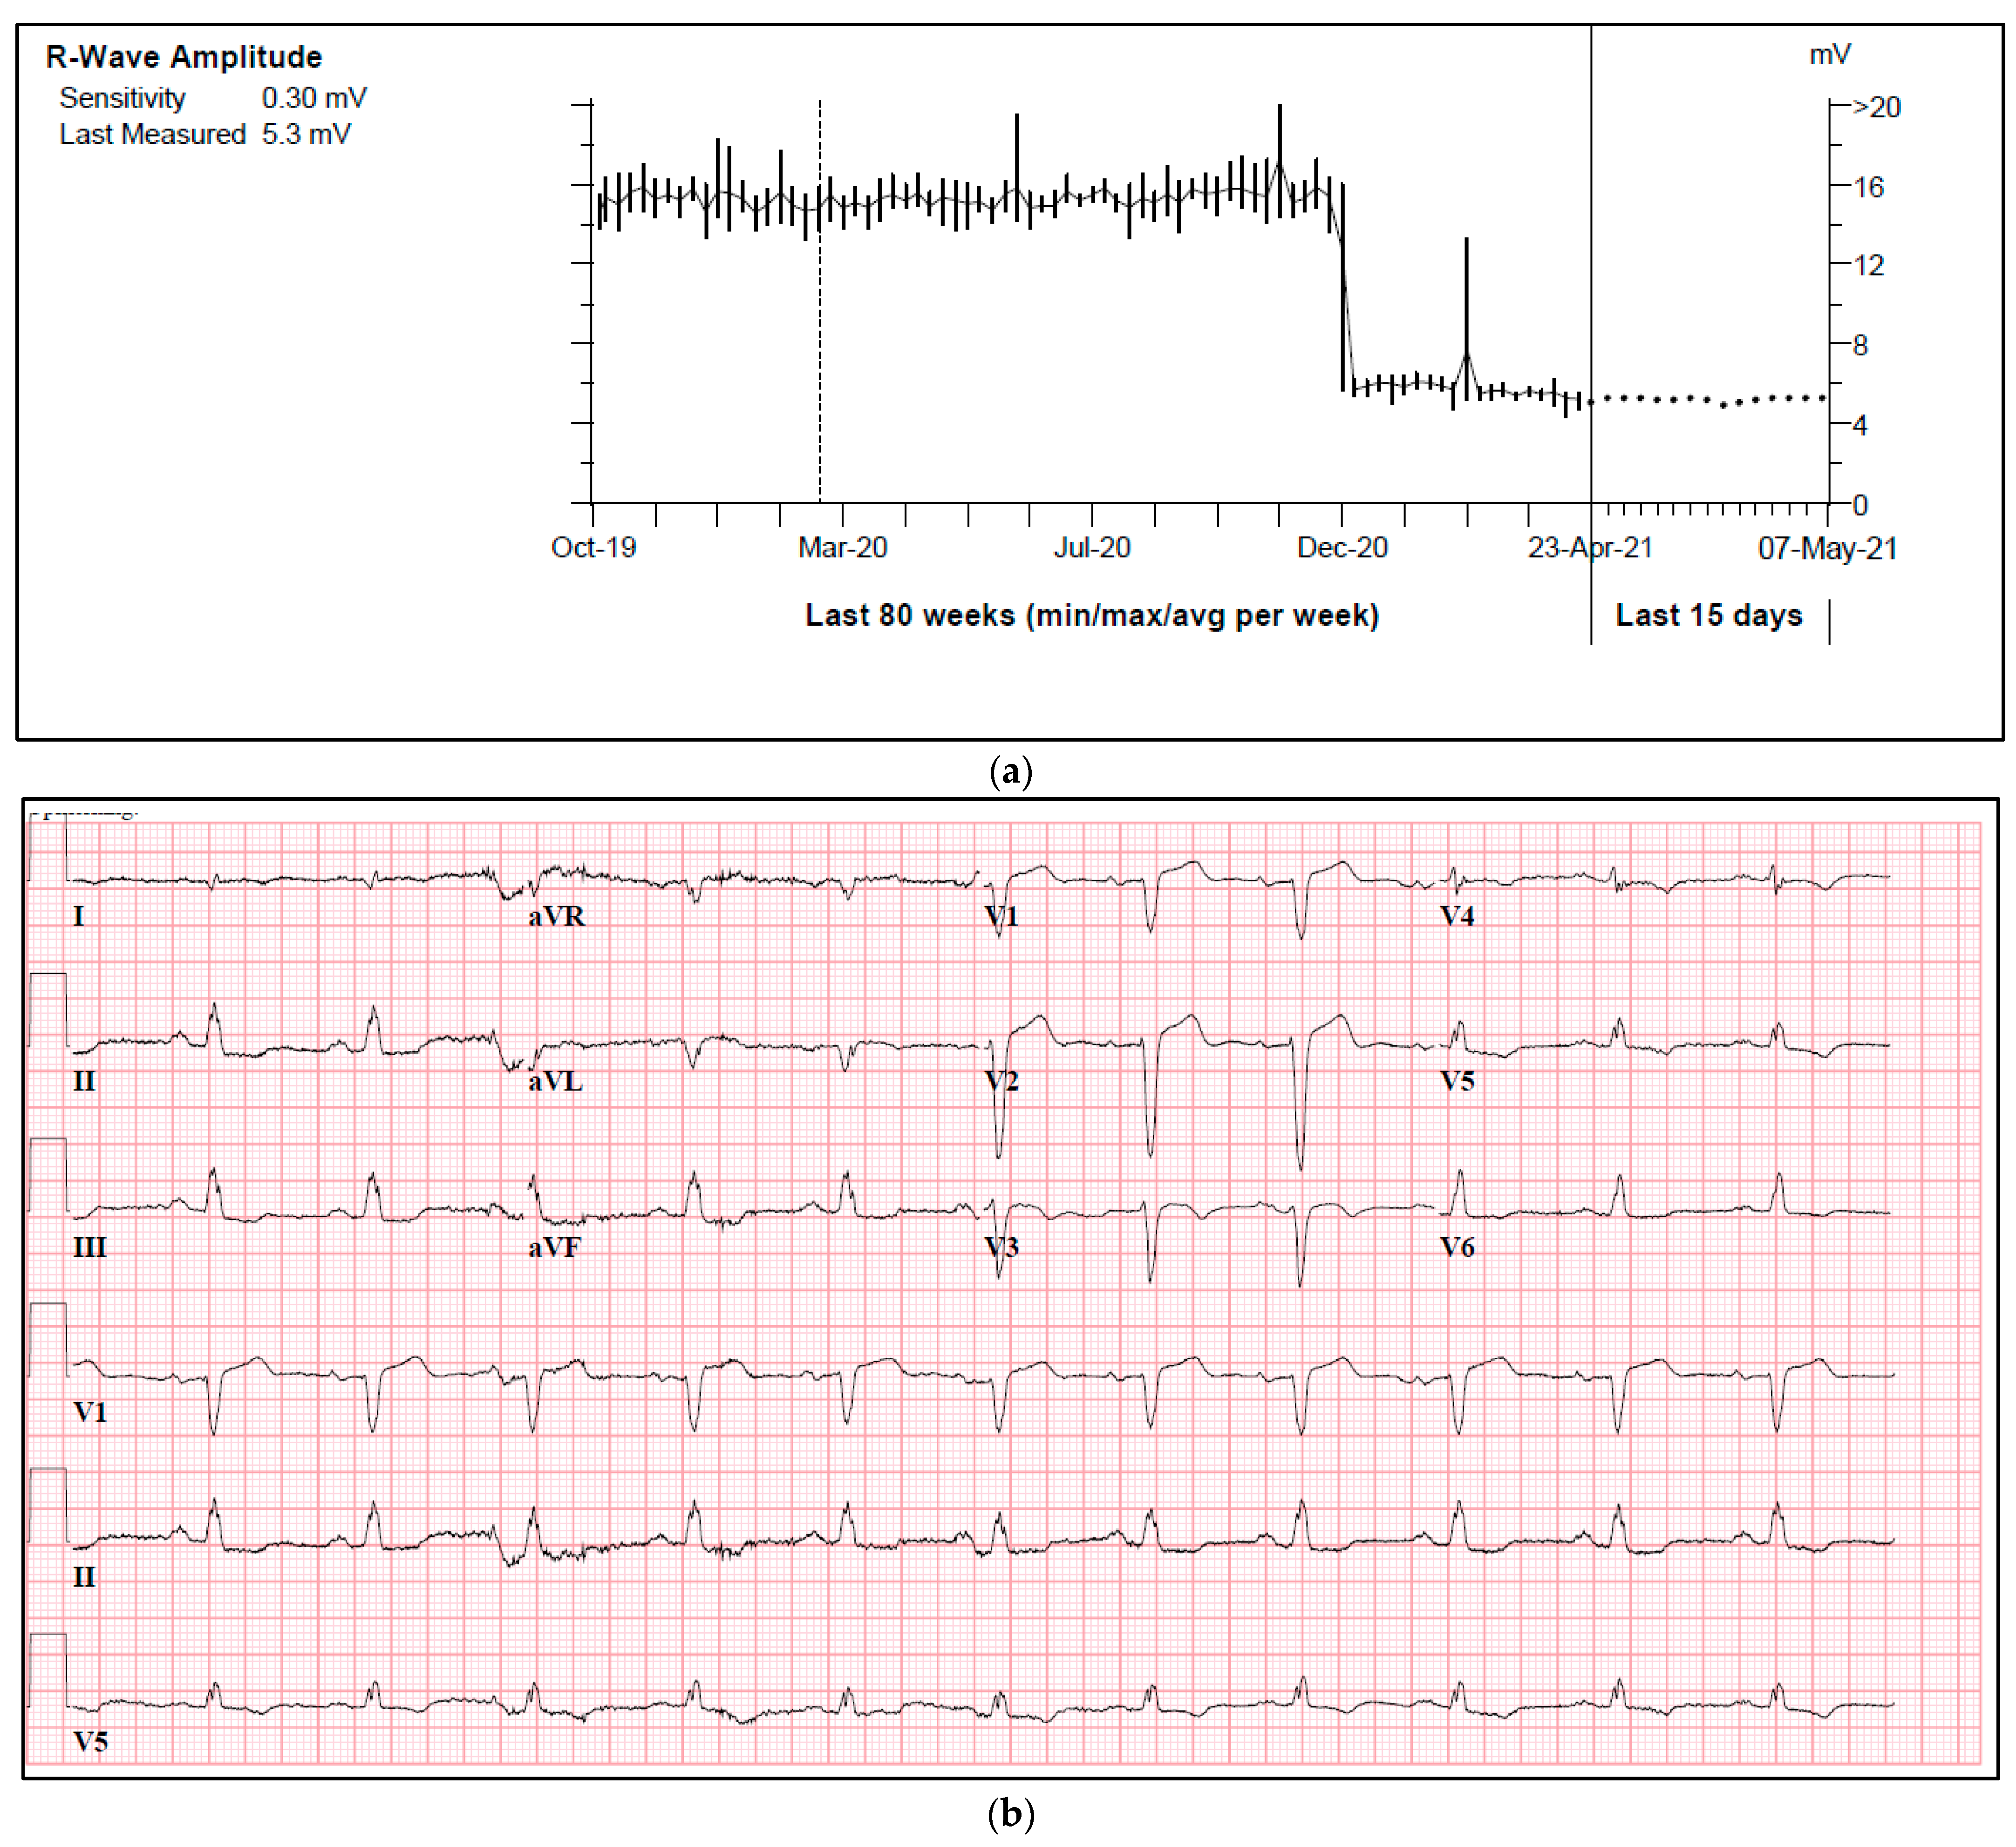

| Intracardiac signals (mV) | Atrial lead > 0.5 mV Ventricular lead > 2–3 mV | Decrease: fibrosis [7], arrhythmogenic cardiomyopathy [18], hyperkalemia [19], and left anterior fascicular block (this review). |